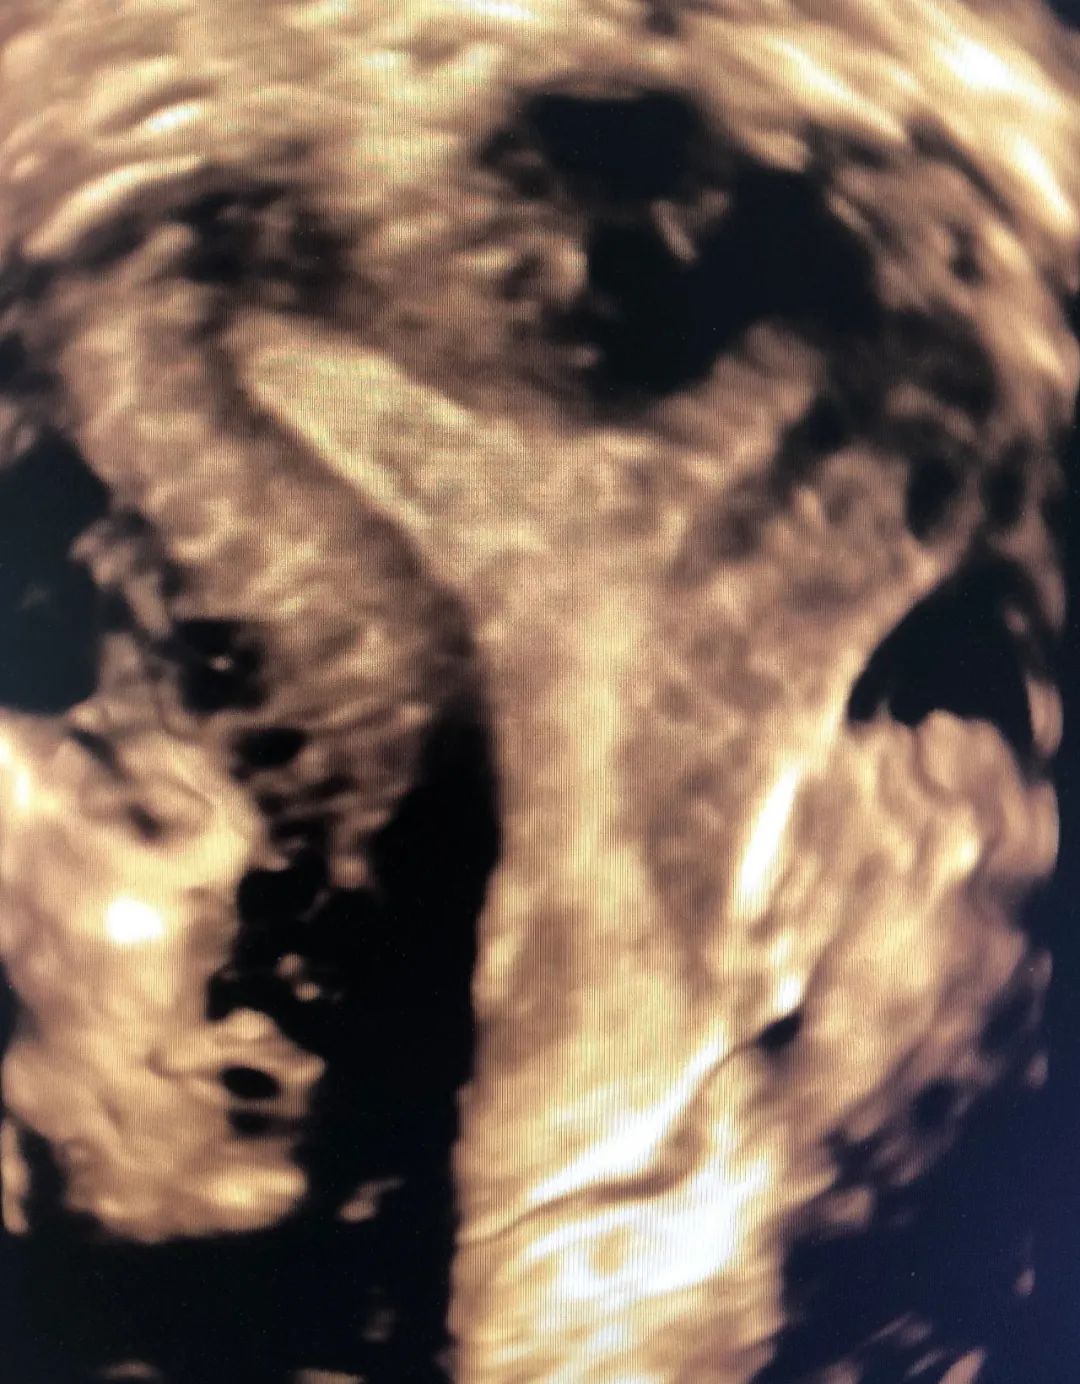

超声诊断弓形子宫 (大荔县妇幼保健院四维彩超)

6月2日,一患者因外院超声诊断不全纵隔子宫来市妇幼院就诊,经常规妇科超声检查并未发现明显纵隔,与患者沟通后行经阴道四维超声检查,得到了清晰的图像诊断为弓形子宫,为妇科临床诊断提供了可靠依据。

腔内四维超声(4D-TVS)是在腔内二维超声基础上,利用计算机处理发展起来的新型超声诊断技术,可以提供更多的诊断信息,具有常规经阴道超声无法比拟的优势,立体直观,功能强大,可实现360度全方位无死角成像,大大弥补了单纯二维腔内超声的不足。

腔内四维超声检查可对先天性子宫畸形(完全或不完全纵隔子宫、弓状子宫、双角子宫、单角子宫、残角子宫等)、宫腔粘连、内膜息肉、粘膜下肌瘤进行诊断及鉴别诊断,还能清晰的观察到节育器的形态、位置,大大提高了超声在妇科疾病诊断中的准确率,为临床医生提供更准确的诊断信息,同时填补了我市在此项技术的空白。